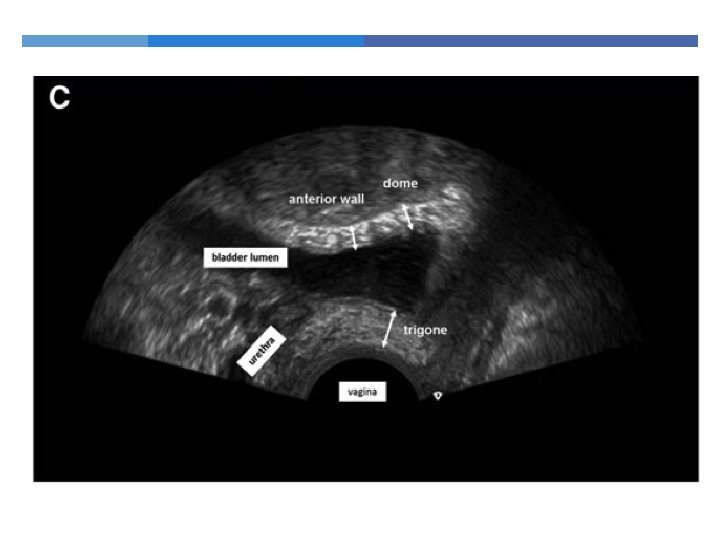

Trigone + Anterior wall +Bladder dome Bladder wall thickness = ________________ 3

3. Bladder wall thickness more than 5 mm suggests Detrusor Overactivity

2. Bladder neck mobility Bladder neck descent of > 2. 5 cm is considered to be hypermobility

4. Funneling

5. Demonstration of stress incontinence